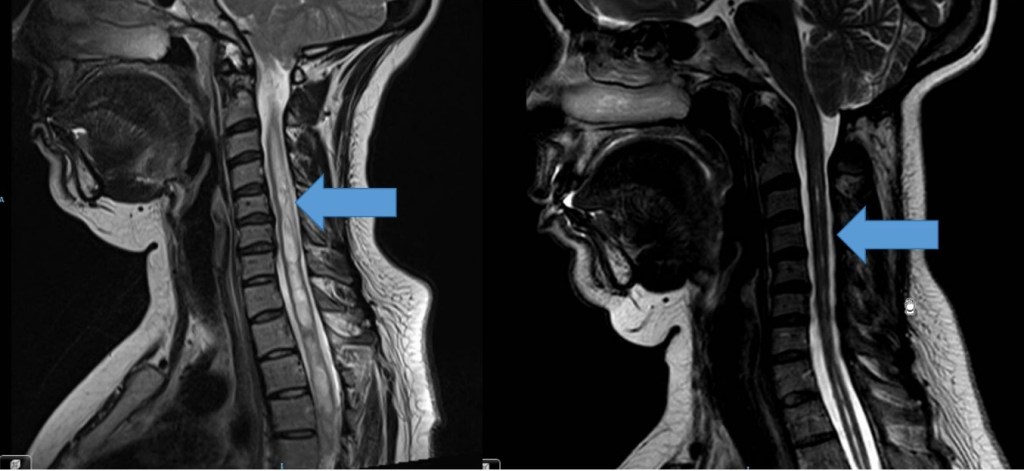

- ¿En qué casos es necesario operar la columna cervical?